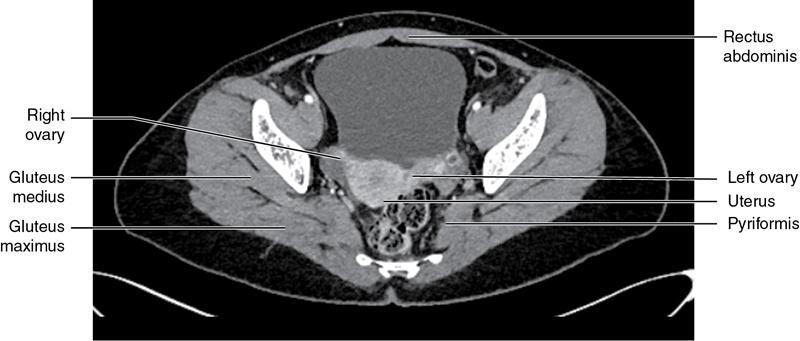

CROSS SECTIONAL ANATOMY OF ABDOMEN Satya Jha NORMAL ANATOMY OF ABDOMEN AND PELVIS Amandeep Singh The two major surfaces: The anterior and posterior layers of the coronary ligament converge on bare area (not covered by peritoneum). Its right and left margins form the right and left triangular ligaments. The right triangular ligament extends toward the diaphragm and separates right subphrenic space from right subhepatic space. The left triangular ligament gives tracts extending to the diaphragm and falciform ligament and does not compartmentalize the left subphrenic space. Ligamentum teres or the obliterated umblical vein is contained in falciform ligament which attaches the liver to anterior abdominal wall. The main portal vein, the proper hepatic artery and the common bile duct are contained within investing peritoneal folds of hepatoduodenal ligament at the porta hepatis (Fig. 7.2.2.1). Liver is divided into eight segments which are functionally independent and have their own vascular supply and biliary drainage. Arterial circulation: The branches of the hepatic artery accompanying the portal veins. Hepatic venous system: The right, middle, and left hepatic veins draining into IVC (Figs. 7.2.2.2 and 7.2.2.3). The gallbladder is a blind pear-shaped muscular membranous sac which is an embryologic derivative of the foregut, is a pouch lying along the undersurface of the liver. The gallbladder fossa is located in the plane of the interlobar fissure, which lies between the right and left hepatic lobes. Its major function is to store and concentrate bile which is produced by the liver. It measures approximately 4 cm in diameter when it is normally distended. Gallbladder is a smaller tubular structure in contracted state. The normal gallbladder wall thickness ranges from 1 to 3 mm. The gallbladder is divided into the fundus, body and neck. Infundibulum is present in the region of neck of the gallbladder, which is called the Hartmann pouch, where gallstones are usually impacted. Intrahepatic biliary radicles (IHBRs) scattered throughout the liver get confluent towards the hilum. They unite to form the right and left main hepatic ducts which further unite to form common hepatic duct (CHD) at the hilum. Common bile duct is formed by the union of cystic duct with common hepatic duct. The main pancreatic duct is joined with the common bile duct to form the ampulla of Vater at the major duodenal papilla (Figs. 7.2.2.4 and 7.2.2.5). Pancreas is located in anterior pararenal space of retroperitoneum anterior to perirenal (Gerota’s) fascia and posterior to parietal peritoneum. It is divided into head, uncinate process, neck, body and tail from right to left. Pancreas lies anterior to portal vein, which marks the point of transition between the body and neck. The region between head of pancreas and second and third parts of duodenum is known as the pancreatic groove. In postnephrectomy cases or with agenesis of kidney or ectopic kidney, pancreas moves posteriorly to partially fill in the empty renal fossa; its soft tissue density should not be mistaken for recurrent tumour. It is located in the pancreatic groove and is bounded superiorly by the duodenal bulb, laterally by second portion of duodenum, inferiorly by third portion of duodenum, medially by superior mesenteric vein and anterior to inferior vena cava. It is a wedge or wedge shaped lying posterior to superior mesenteric artery and vein. It is an imaginary junction between the head and body and lies directly over the junction of the splenic vein and superior mesenteric vein. It is located posterior to the lesser sac and anterior to the aorta, left adrenal gland, left kidney, and renal vessels and runs obliquely upward to the left of the superior mesenteric vessels. It is situated median to the colonic flexure and anterior to the left kidney. It is located in close proximity to the splenic hilum without a notable relation with the body of pancreas. It is seen anterior to the left kidney and median to the colonic flexure. The distal part of the tail passes between the peritoneal layers of the splenorenal ligament (Fig. 7.2.2.6 and 7.2.2.7).